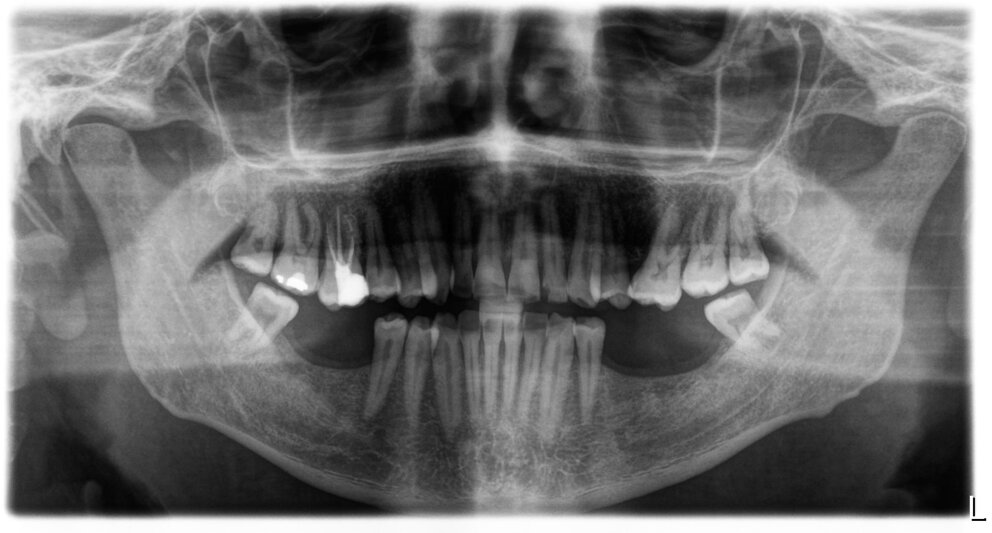

OPT pre operatoriaProgettazione computer guidataOPT post operatpria in seguito all'inserimento degli impianti